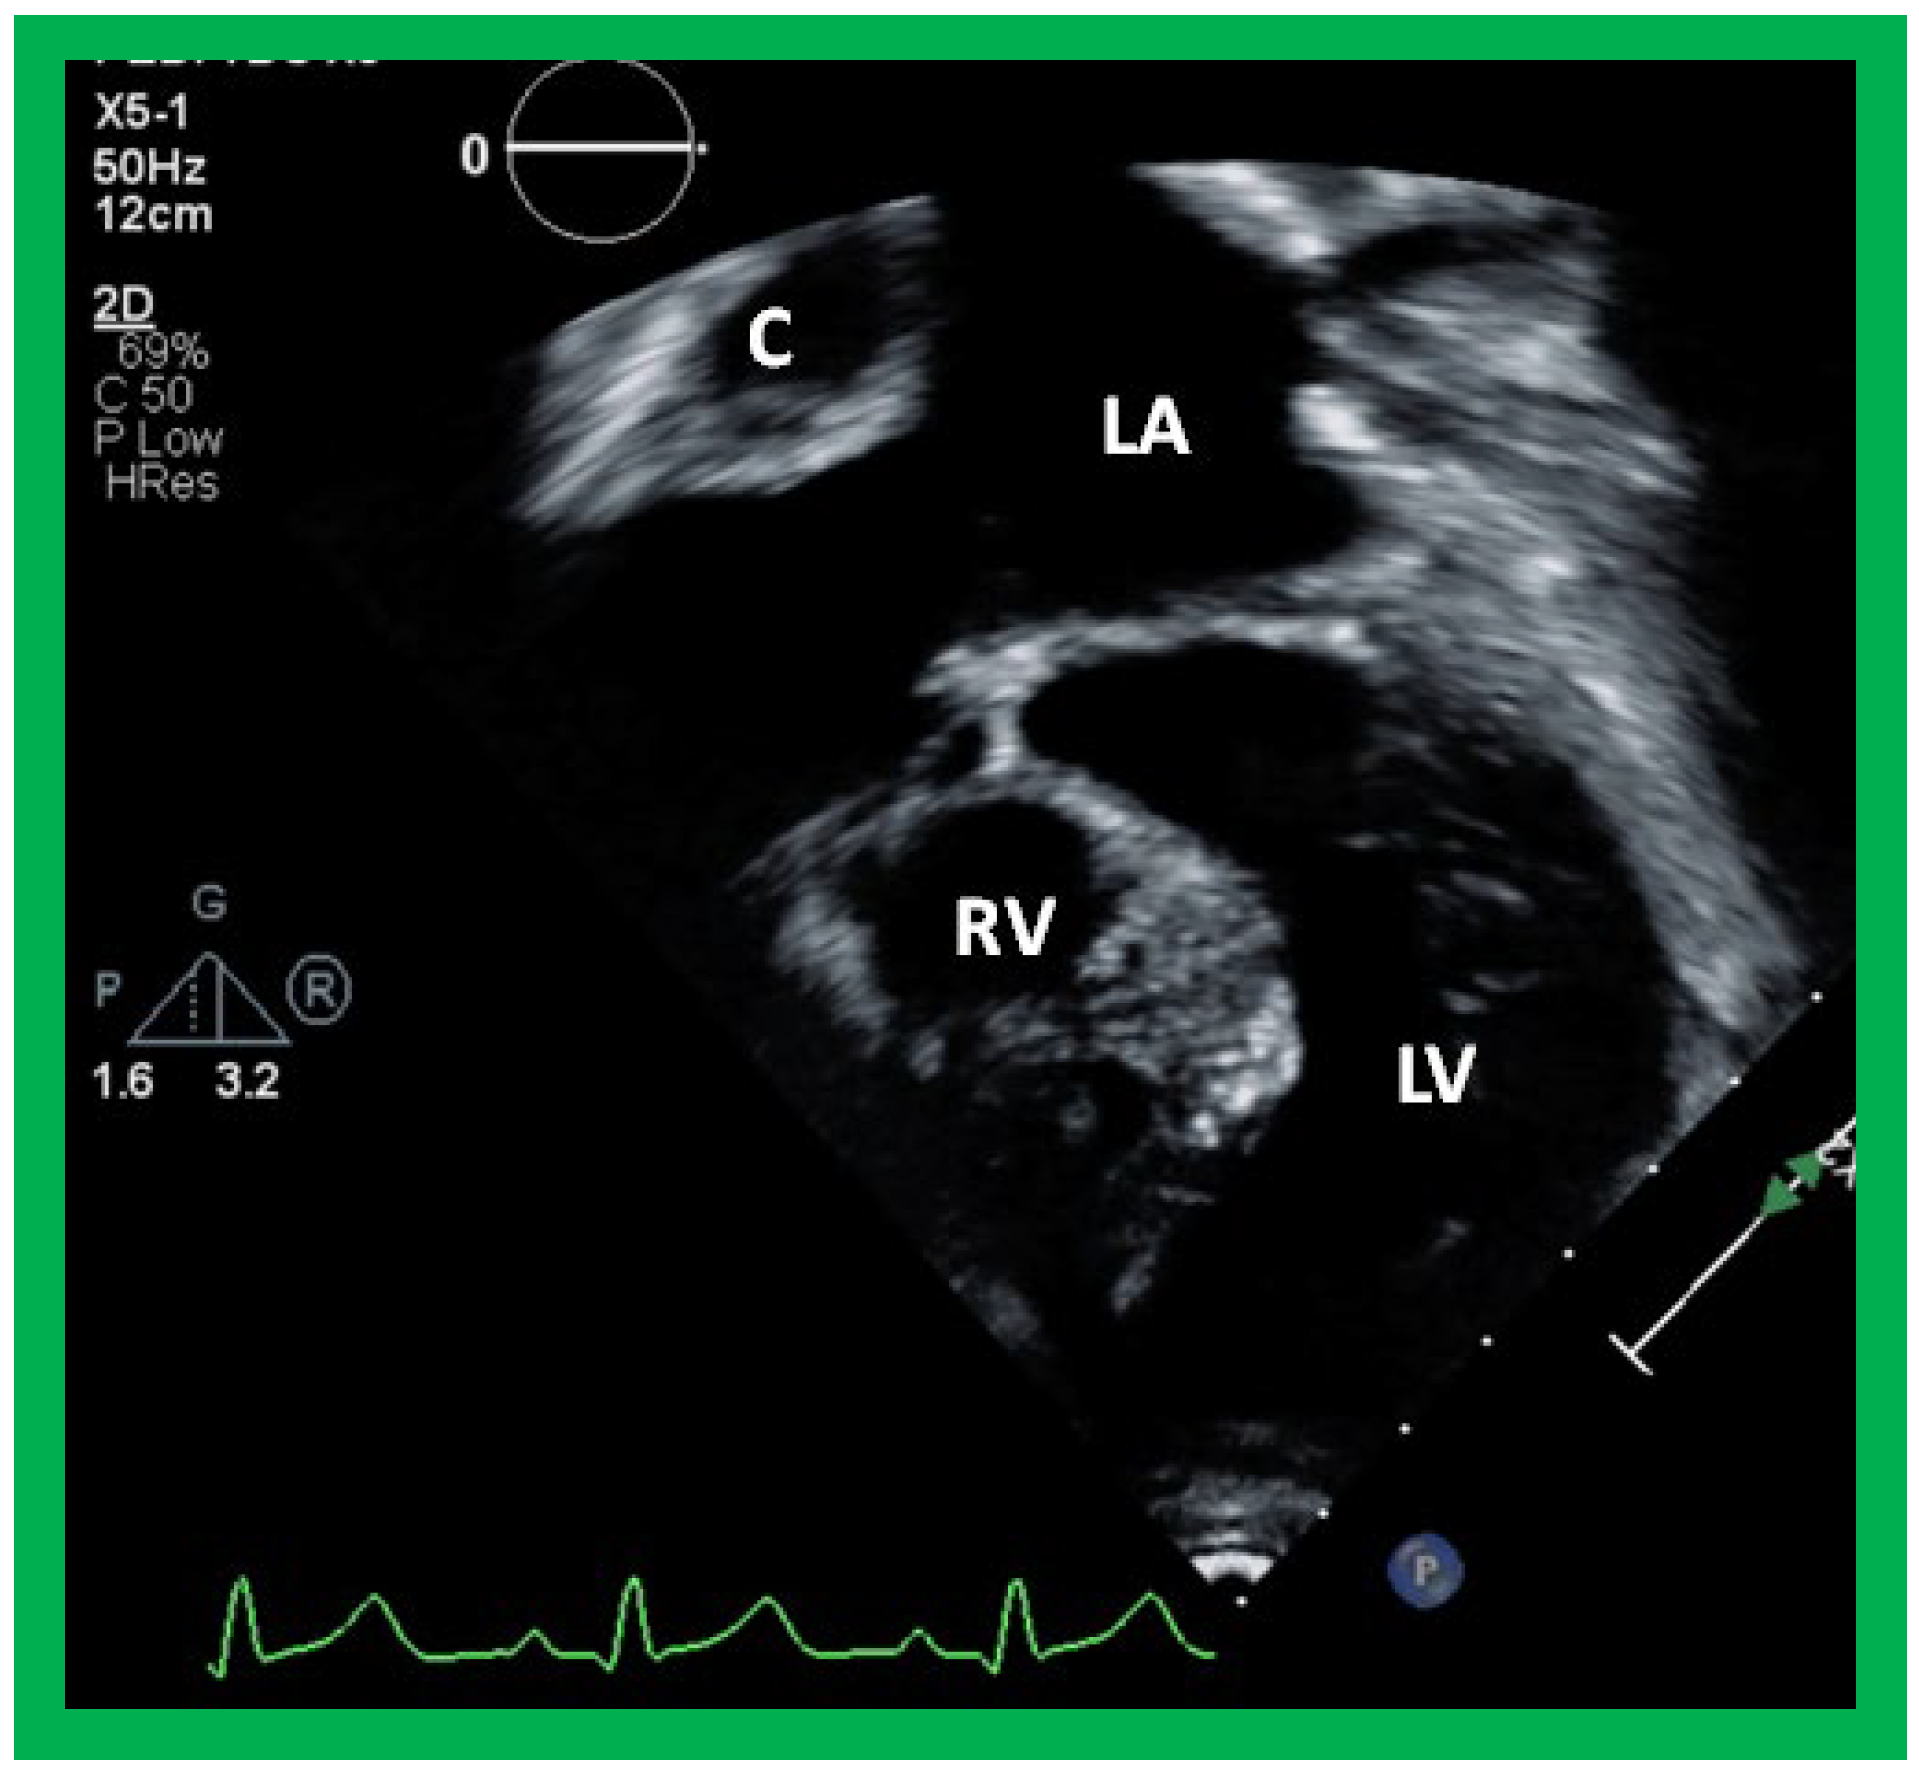

Following the demonstration of the atretic tricuspid valve, the sizes of the cardiac chambers are evaluated both by M-mode (Z scores) and 2D echocardiography; an enlarged RA, LA and LV and a small RV are seen (Figure 4, Figure 5 and Figure 6). Pulsed (not shown) and color Doppler (Figure 9) studies are helpful in illustrating right to left shunt across a PFO or an ASD.

Figure 5. Apical four chamber view pictures of an infant with tricuspid atresia with ostium primum atrial septal defect (large arrow in the middle of (B)). Note the small right ventricle (RV) and a ventricular septal defect (small arrow in (A,B)). LA, left atrium; LV, left ventricle; RA, right atrium. Reproduced from Reference [28].